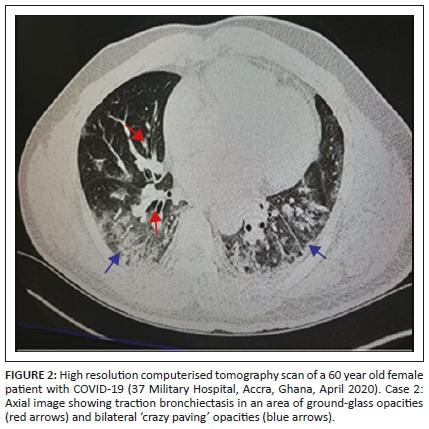

She had a marginally increased neutrophil-white blood cell count and a high D-dimer of 1.26 ug/mL (fibrinogen equivalent unit; normal limit 0.0-0.5). Her liver function test showed deranged liver enzymes. However, renal function tests, C-reactive protein (3.6) and troponin were normal. A computerised tomogram scan was done, the pulmonary vessels were reported as normal (Figure 2).

The PCR results for COVID-19 were returned as negative three days after sample collection. She was therefore transferred from the isolation unit to a general medical ward. She later suddenly developed severe respiratory distress, started desaturating and later died. An academic autopsy was ordered by the attending clinical team who queried the PCR COVID-19 result (Table 1).